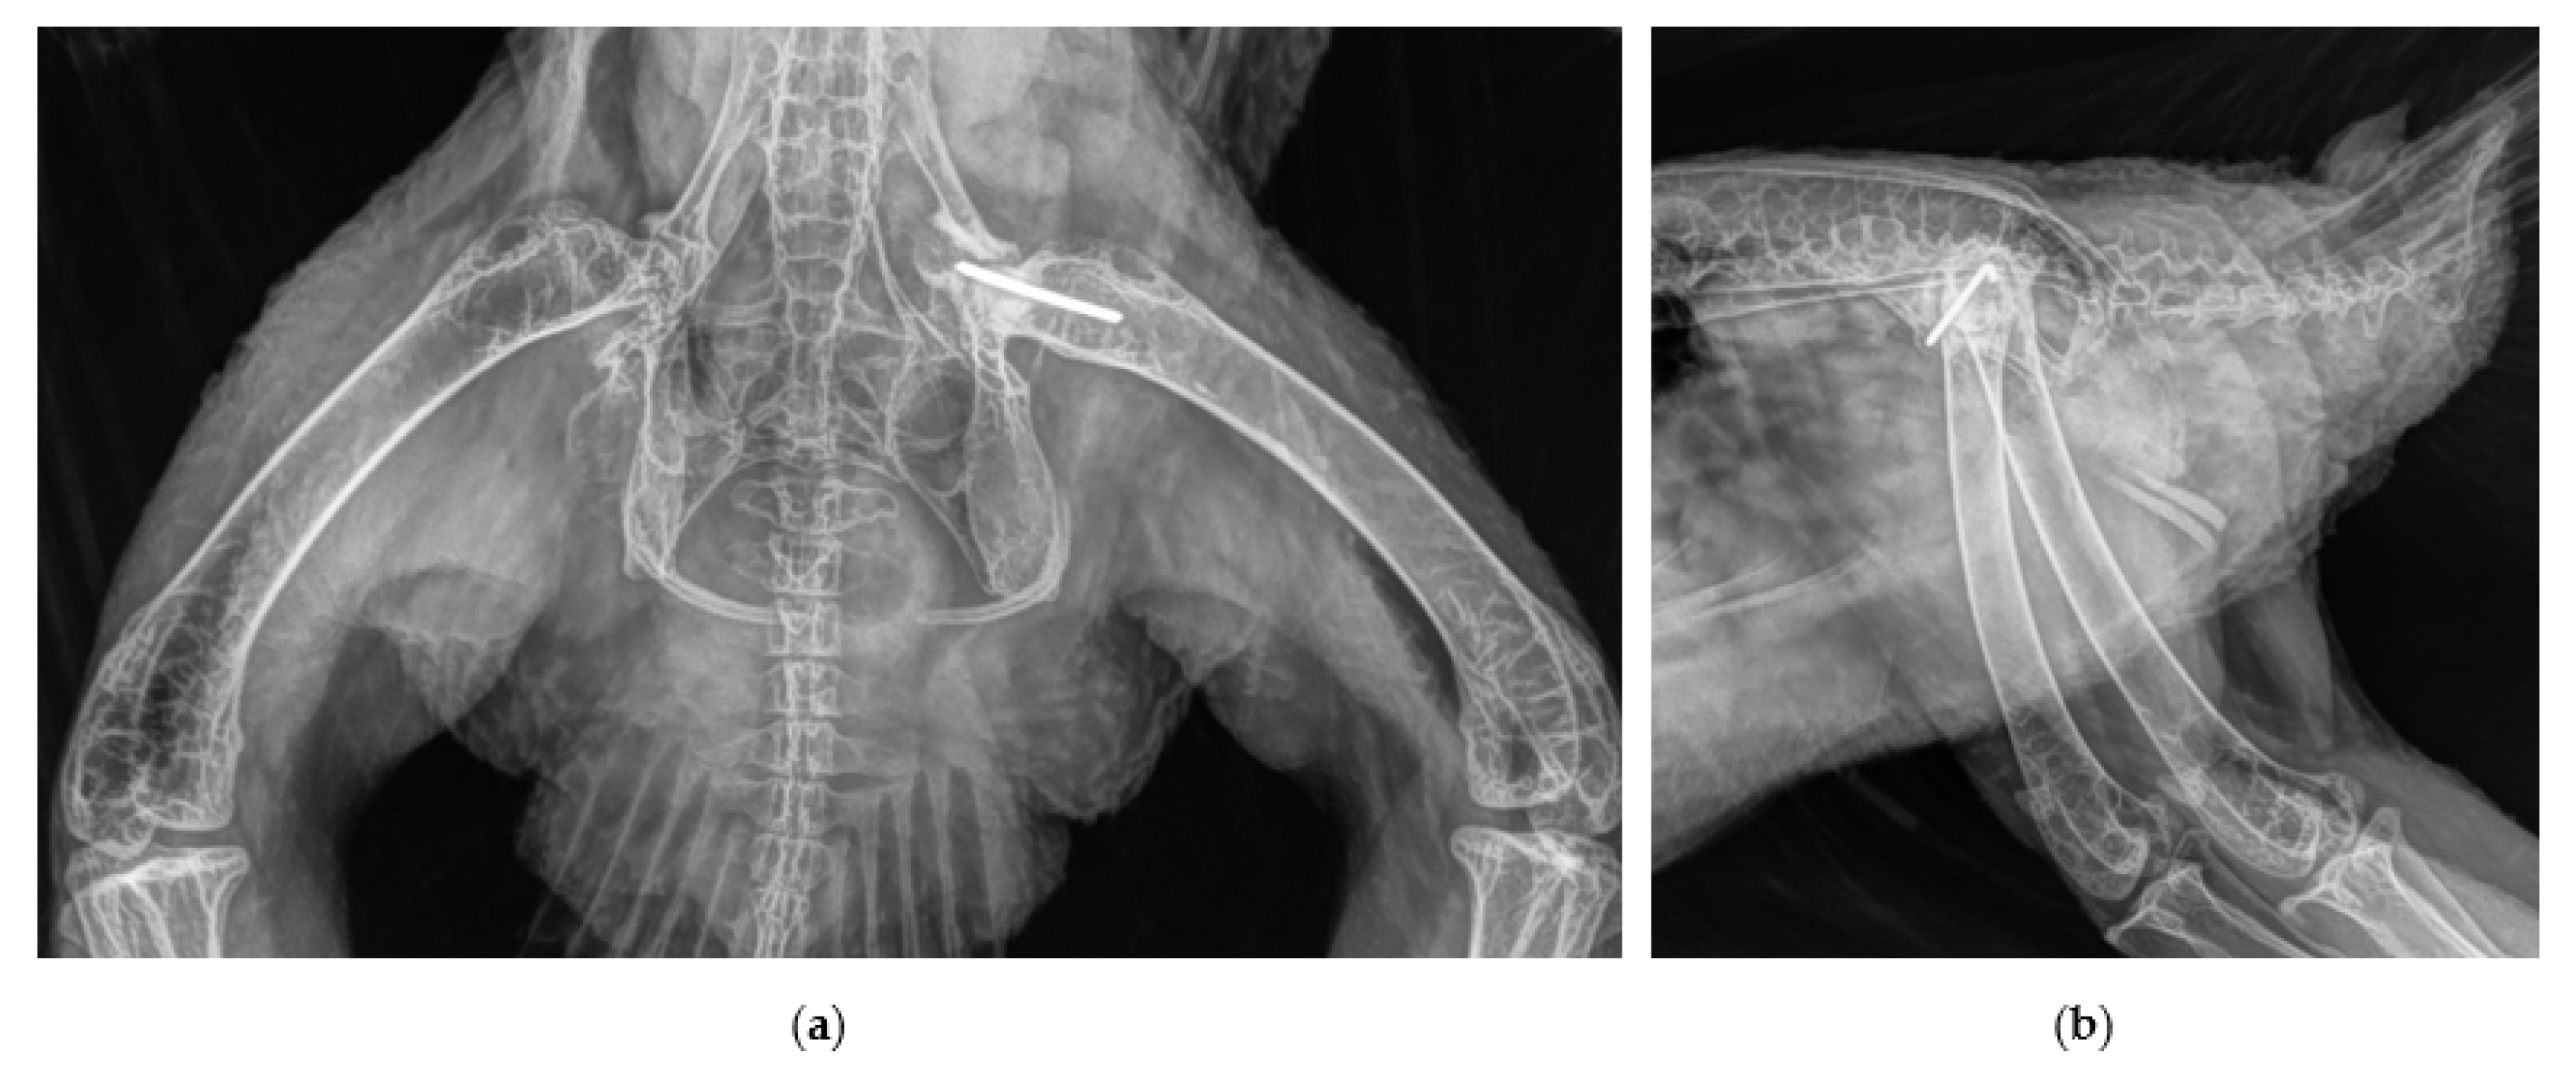

2.2. Surgical Procedure and Post-Surgery Management

3. Discussion